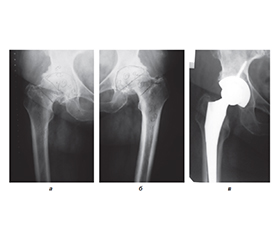

Сучасний підхід до профілактики венозних тромбоемболічних ускладнень у хворих до та після операції ендопротезування кульшового суглоб

Актуальність. Проблема діагностики та профілактики післяопераційних коагулопатій доволі актуальна у сучасній ортопедії, оскільки в Україні й за кордоном зростає кількість операцій ендопротезування пацієнтам з різною патологією кульшових суглобів. Мета: на основі аналізу факторів ризику розвитку венозних тромбоемболічних ускладнень (ВТЕУ) у хворих із патологією кульшового суглоба до та після операції ендопротезування обґрунтувати комплекс заходів їх профілактики. Матеріали та методи. Пацієнтів, яким проводилось ендопротезування кульшового суглоба, було розділено на групи: І група — низького ступеня ризику віком 20–40 років (n = 13); ІІ група — помірного ступеня ризику віком 41–60 років (n = 45); ІІІ група — високого ступеня ризику віком 61–80 років (n = 42). Для оцінки ступеня ризику тромботичних ускладнень використовували методику, аналогічну шкалі J.F. Caprini. Результати. Аналіз тромботичних ускладнень у досліджуваних групах хворих після операції тотального ендопротезування кульшового суглоба у порівнянні з даними наукової літератури показав, що ускладнення у вигляді тромбоемболії легеневої артерії у наших пацієнтів не спостерігалося, а за даними літератури — від 1,08 до 30 %, тромбози глибоких вен нижніх кінцівок у нашому дослідженні — 4,65 %, а за даними літератури — 10–20 % (зменшення в середньому на 5,35 %). Набряк нижніх кінцівок (хронічна венозна недостатність) у наших пацієнтів — 15,5–20,9 %, за даними літератури — 17–25 % (зменшення в середньому на 3 %). Висновки. Тромбопрофілактика венозних тромбоемболічних ускладнень при операції тотального ендопротезування кульшового суглоба потребує індивідуального підходу до пацієнтів з огляду на фактори ризику як у доопераційному, так і у післяопераційному періодах. Запропонована нами програма профілактики в досліджуваних пацієнтів, якщо порівнювати з даними літератури, дозволила зменшити кількість тромботичних ускладнень: у І групі хворих з низьким ступенем ризику ці ускладнення не відмічалися, у ІІ і ІІІ групах тромбози глибоких вен нижніх кінцівок зменшилися на 5,35 %, набряки нижніх кінцівок — на 3 %, гематоми у ділянці операції — на 1,5 %. Отримані дані свідчать про ефективність і доцільність застосування запропонованого нами комплексу заходів тромбопрофілактики у хворих після ендопротезування кульшового суглоба.

Background. The problem of diagnosis and prevention of postoperative coagulopathies is quite relevant in modern orthopaedics, since an increasing number of patients with various pathologies of the hip joints undergo arthroplasty both in Ukraine and abroad. The purpose: based on the analysis of risk factors for the development of venous thromboembolic complications in patients with hip joint pathology after arthroplasty, to substantiate a set of measures for their prevention. Materials and methods. Patients who underwent hip arthroplasty were divided into the following groups: group I — low risk, 20–40 years old (n = 13); group II — moderate risk, 41–60 years old (n = 45); group III — high risk, 61–80 years old (n = 42). To assess the risk of thrombotic complications, a method similar to the J.A. Caprini score was used. Results. Analysis of thrombotic complications in the studied groups of patients after total hip replacement compared to the data of the scientific literature showed that complications in the form of pulmonary embolism were not observed in our patients. According to the literature, they are found in 1.08–30 % of cases. Deep vein thrombosis of the lower extremities was detected in 4.65 and 10–20 % of patients, respectively (an average decrease of 5.35 %), oedema of the lower extremities (chronic venous insufficiency) — in 15.5–20.9 and 17–25 % of cases (an average decrease of 3 %). Conclusions. Thromboprophylaxis of venous thromboembolic complications during total hip arthroplasty requires an individual approach to patients, taking into account risk factors both in the pre-operative and postoperative periods. The prevention program we proposed in the studied patients, compared to the literature data, allowed us to reduce the number of thrombotic complications: in group I of patients with a low risk, these complications were not observed, in groups II and III, deep vein thrombosis of the lower extremities decreased by 5.35 %, oedema of the lower extremities by 3 %, hematomas in the surgical area by 1.5 %. The data obtained indicate the effectiveness and feasibility of using a set of thromboprophylaxis measures proposed by us in patients after hip arthroplasty.